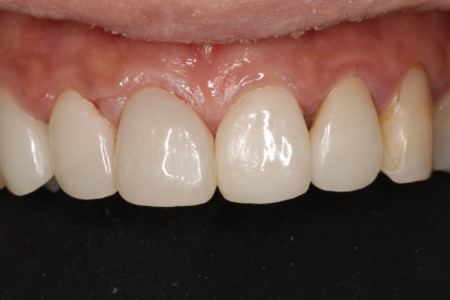

• 治療前

• 治療後